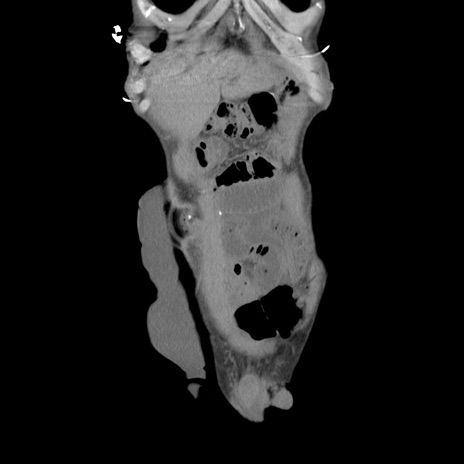

症例11(冠状断像)

【症例】 60歳代男性

【主訴】 下腹部痛

【現病歴】 本日夜中より下腹部痛の症状認め、受診。

【既往歴】 膀胱癌(膀胱全摘+尿管皮膚瘻術) 、胃癌術後

【身体所見】 BT 35.3℃、PR 58/min、BP 136/98mHg、腹部平坦、軟、腸蠕動音±、ストマ留置あり、左上腹部~正中部に圧痛あり、反跳痛なし。

【データ】WBC 5100、CRP0.01